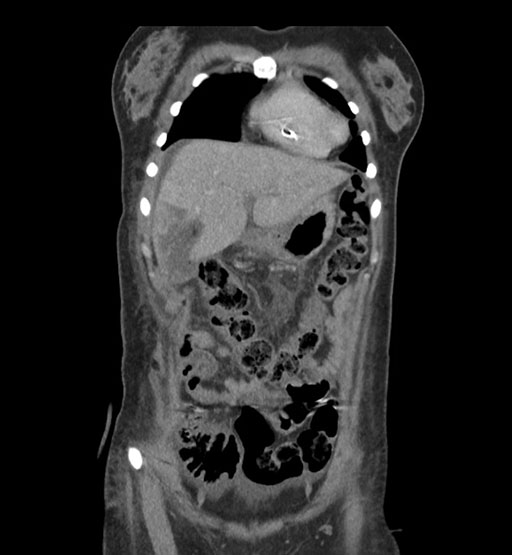

Imaging Analysis

Look through the patient's CT scan to identify any areas of concern for the necessary procedure.

Coronal Arterial

Coronal Venous

Based on initial findings, which issue(s) would you be most concerned about?